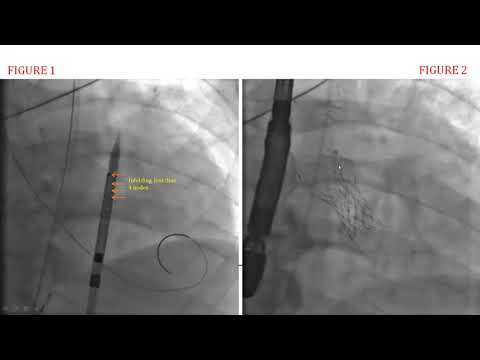

Device anchoring with a goose neck snare during Valve in Valve #TAVI for uncrossable valve.

Incomplete Expansion of a Self-Expanding TAVR Device Leading to Hemodynamic collapse

26mm Evolut-PRO CoreValve TAVR - March 13, 2018